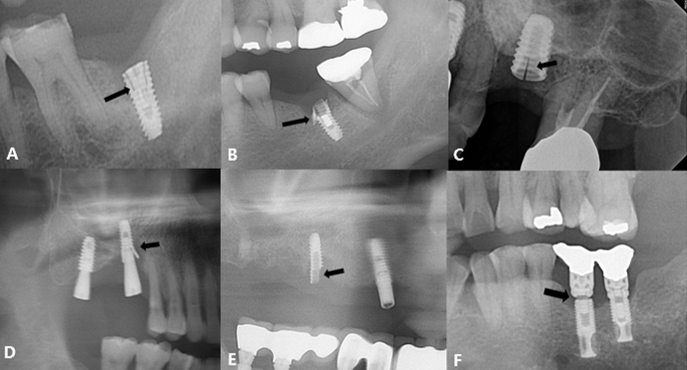

This study included 22 men and 11 women (mean age, 60.8 years; range, 33–82 years) with a total of 43 fractured implants (Table 1 and Fig. 1). The incidence of implant fracture was two times higher in men than in women (M:F = 22:11). Among the 33 patients, seven had external-connection implants, of which 12 were fractured (Fig. 2). Internal-connection implants were used in 26 patients, of which 31 were fractured (Fig. 3). Of the 26 patients with internal-connection implants, bone- and tissue-level fractures were observed in 23 and 3 cases, respectively. Maxillary and mandibular implant fracture occurred in 15 and 18 patients, respectively. Single- and multiple-implant fractures were observed in 26 and 7 patients, respectively. Except for two cases of anterior-implant fracture (Cases 9 and 12), all fractured implants were located in the premolar and molar regions (Table 1). In case 10, the fractured posterior single implant was removed through a typical implant removal process and socket preservation was performed using Bonplug® (Inobone Co.) (Fig. 4). Case 12 involved an anterior single-implant fracture with a clear fracture line (Fig. 5). In case 20, multiple fractured posterior implants were removed using an elevator (Fig. 6). In case 22, two fractured posterior implants were removed, and bone grafting was performed (Fig. 7).